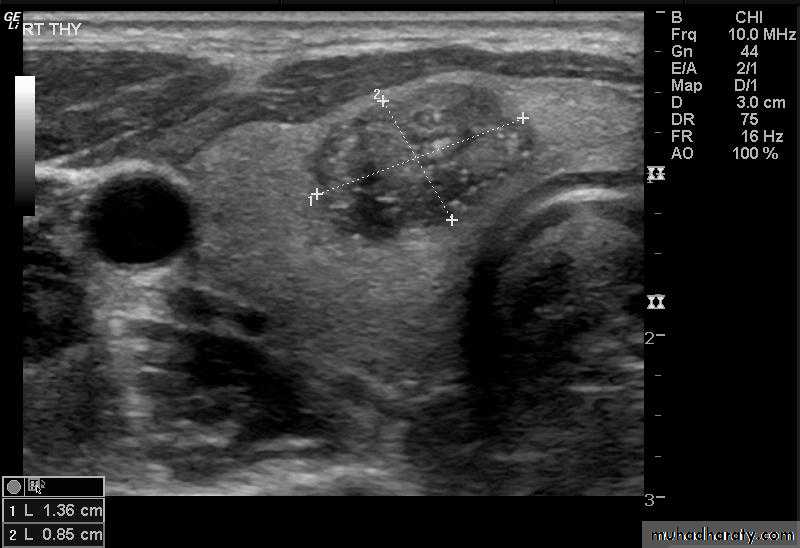

• US is the investigation of first choice.

• US with high-resolution equipment has a high sensitivity (80–90 %) for the detection of parathyroid adenoma.• US appearance of parathyroid adenoma is a well-defined hypoechoic mass usually of around 1.0–1.5 cm in diameter.

• Most parathyroid adenomas lie behind or immediately below the thyroid gland.